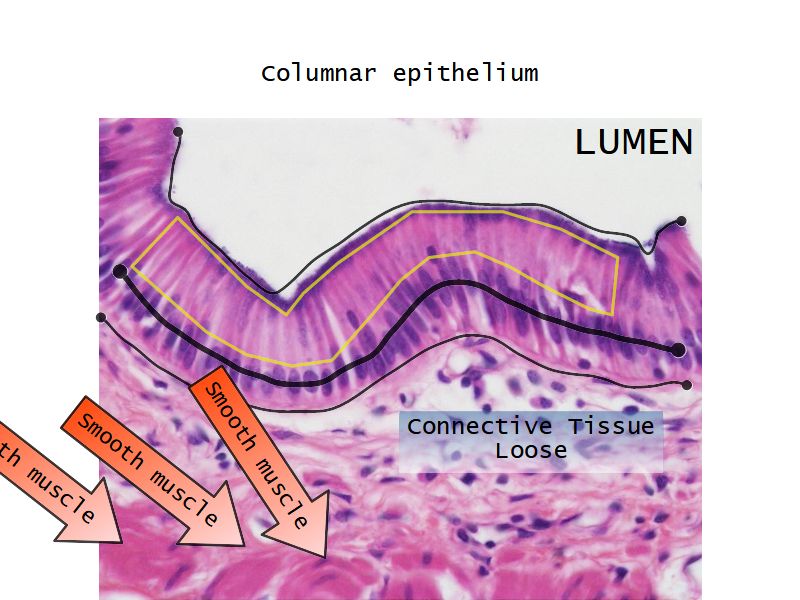

Respiratory epithelium

- Columnar